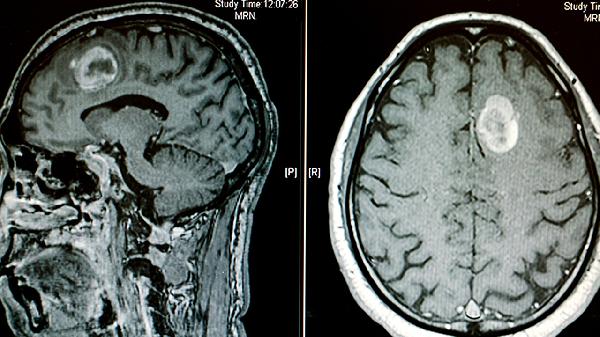

MRI是脑癌诊断的金标准,尤其增强MRI对软组织分辨率更高。多序列成像能清晰显示肿瘤与周围脑组织的界限,弥散加权成像可鉴别肿瘤良恶性。磁共振波谱分析还能检测肿瘤代谢物变化,对胶质瘤分级有重要价值。